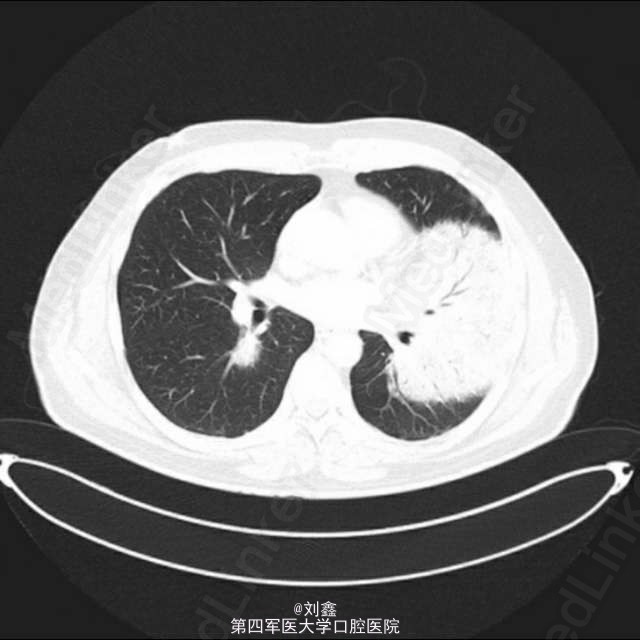

患者,男性,54 岁,6 周前因轻度呼吸困难、全身不适伴干咳被诊断为社区获得性肺炎,经对症治疗后无好转。目前考虑为不吸收性肺炎。病程中患者曾有三次轻度咳血,但无体重减轻、发热或任何其他全身症状。患者不吸烟,有高脂血症,现正接受降脂治疗。 该患者的一般临床检查未发现异常,KPS 80 分。体格检查在左下肺区闻及啰音和支气管呼吸音。 数次胸片检查均提示有左下肺浸润影,且经治疗后无改变。胸部 CT 提示左肺下叶有广泛实变,相对应的右肺下叶上段有实变病灶。血像检查未发现异常改变。